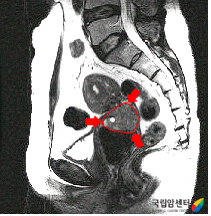

전산화단층촬영검사(CT) 및 자기공명영상(MRI)

내진, 방광경검사, 에스결장경검사 등으로는 자궁경부암 치료방법 및 예후 결정에 가장 중요한 자궁경부 주위조직의 침윤 및 림프절 전이 여부를 알기 어렵기 때문에 전산화단층촬영(CT), 자기공명영상(MRI) 등을 시행하고 있습니다.

질 상부를 침범한 자궁경부암 환자의 MRI 소견 이미지

[질 상부를 침범한 자궁경부암 환자의 MRI 소견]